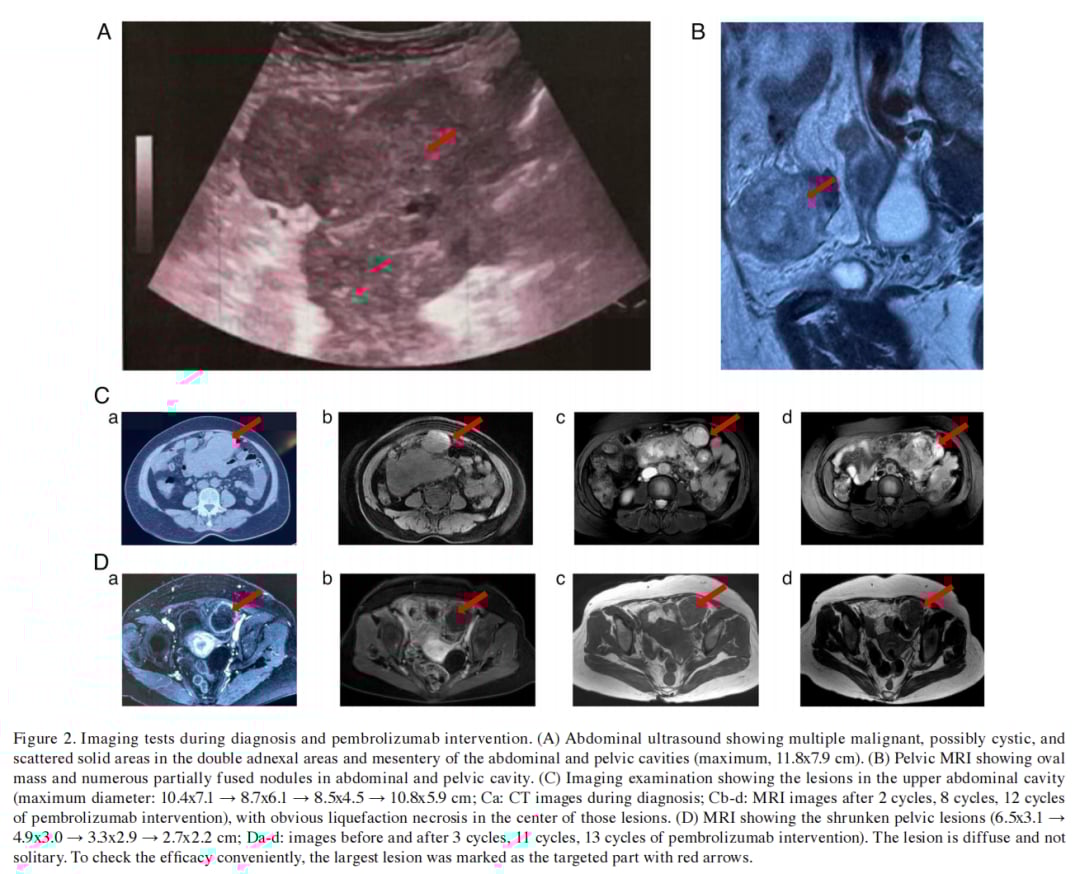

患者在接受帕博利珠单抗治疗后,效果令人惊喜。第一周期治疗后,困扰患者数月的发热症状完全缓解。后续治疗中,盆腔肿块及结节灶明显缩小,病灶中心出现坏死。根据iRECIST v1.1标准,患者对帕博利珠单抗持续保持疾病稳定(SD)状态,无进展生存期(PFS)长达10.0个月。尽管后续尝试了培美曲塞、白蛋白结合型紫杉醇联合帕博利珠单抗、安罗替尼联合帕博利珠单抗等方案,但患者最终的总生存期(OS)达到了26.2个月,这对于伴有副肿瘤综合征的MPEM患者而言,创下了新的生存记录。

▲图2 诊断及帕博利珠单抗干预期间的影像学检查